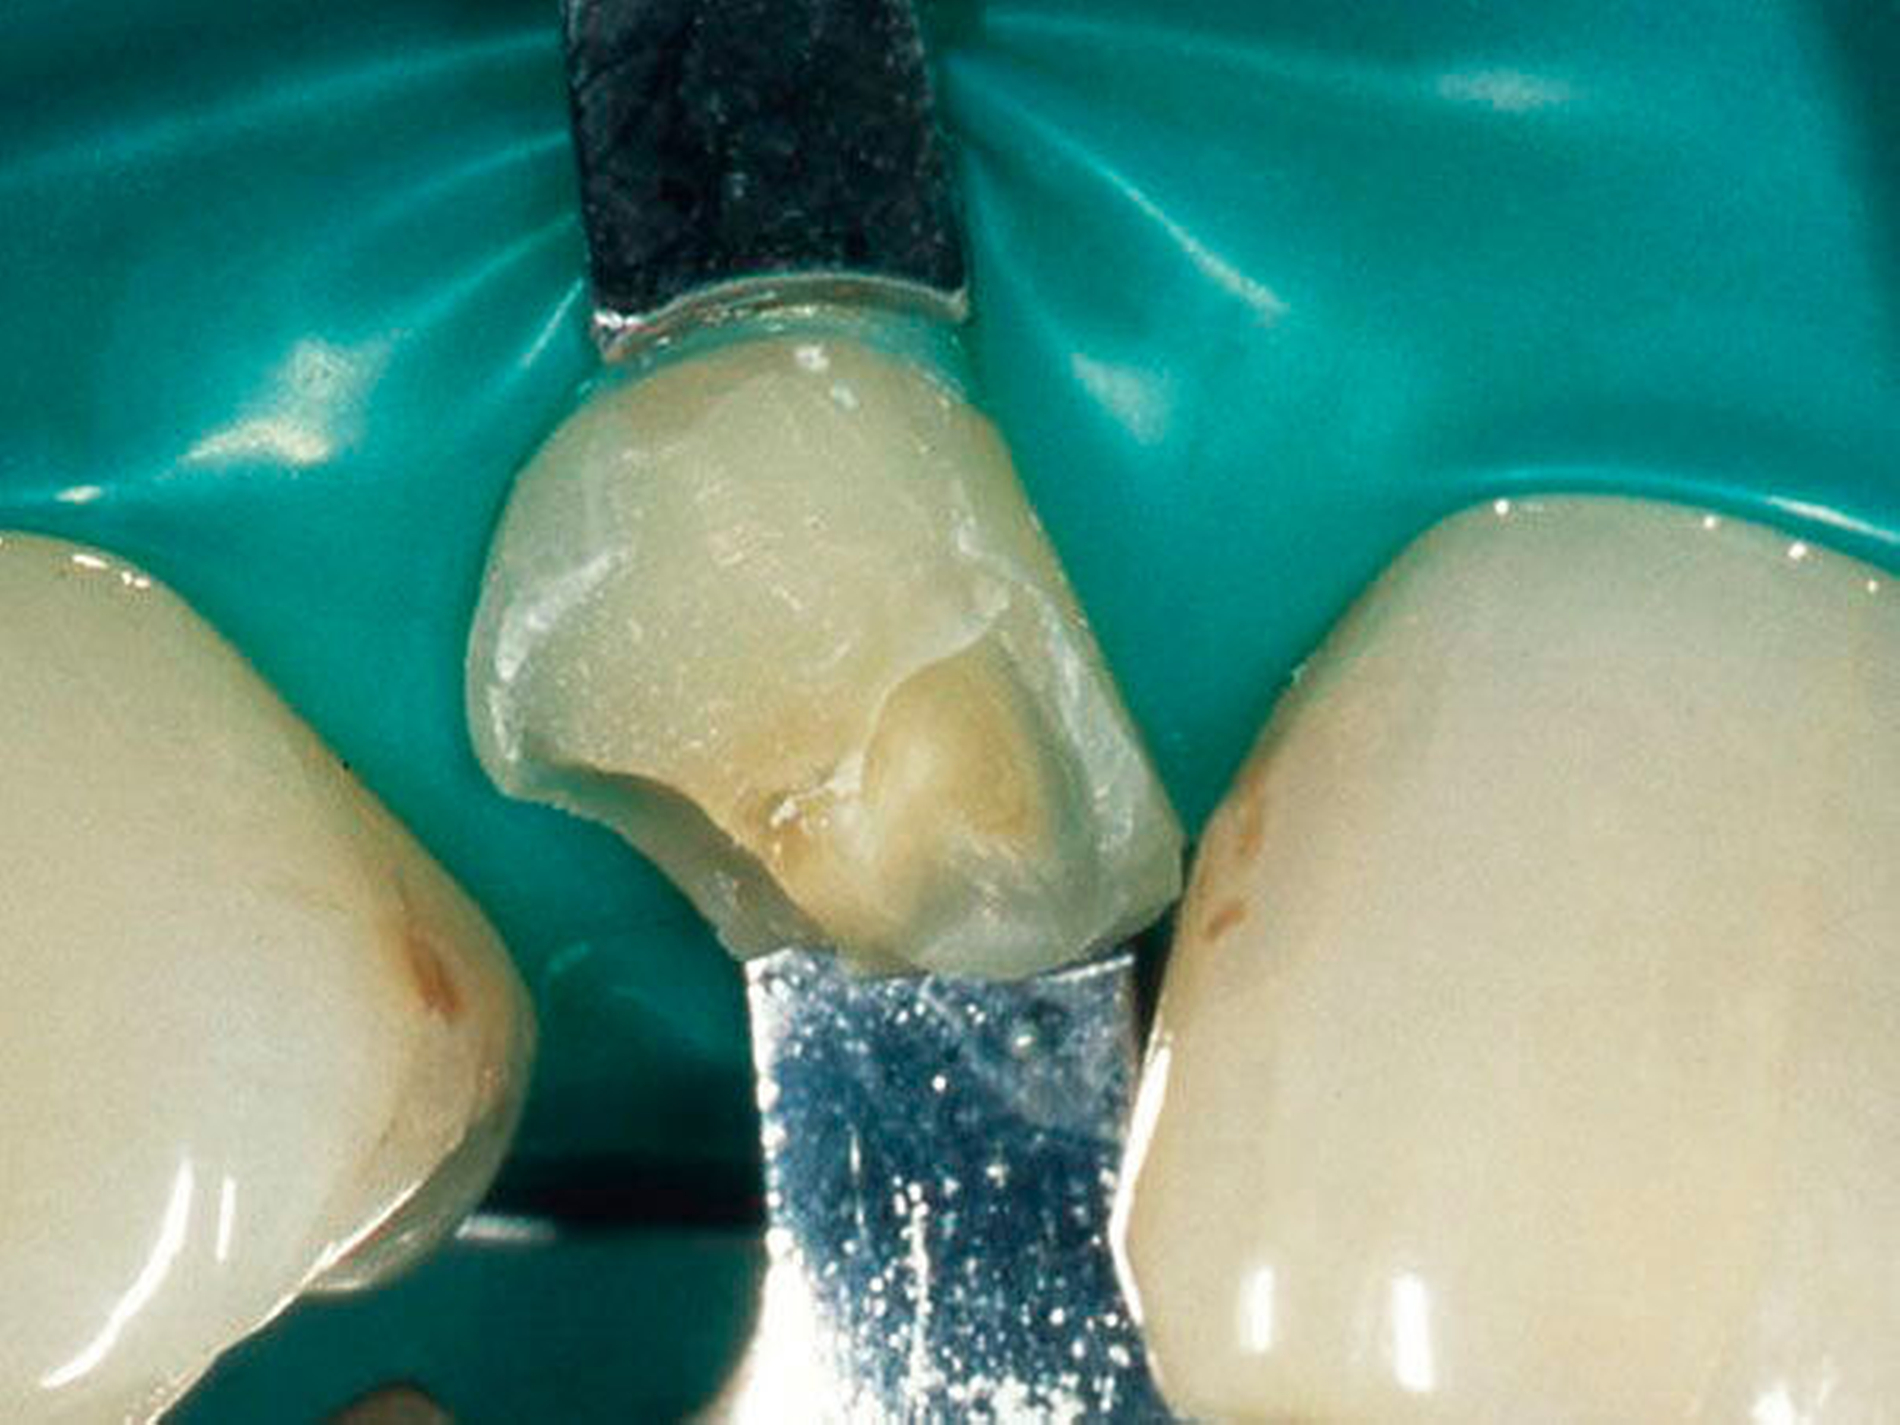

Abbildung 2: Direkte Teilüberkronung im Seitenzahnbereich (R1-Technik)

In den Abbildungen 1 bis 3 werden Optionen für frugale Interventionen auf restaurativem Sektor aufgeführt. Es handelt sich um direkte Vollüberkronungen im Frontzahnbereich (hier: hergestellt in R1-Technik / einphasig) (Abbildung 1), direkte Teilüberkronungen im Seitenzahnbereich (hier: hergestellt in R1-Technik / einphasig) (Abbildung 2), Reparatur-Restaurationen im Seitenzahnbereich (hier: hergestellt in R2-Technik / zweiphasig) (Abbildung 3). Technische Einzelheiten zur Vorgehensweise und den Ergebnissen sind an anderer Stelle beschrieben (Literatur siehe oben).

Für die in Abbildung 2 dargestellte Situation eines tief zerstörten Prämolaren gelten ähnliche Charakteristika. Es gibt in der restaurativen Zahnheilkunde viele Neuerungen, die das Behandlungsspektrum vergrößert haben. Dazu zählen unter anderem:

ein- oder zweiphasiges Vorgehen je nach Defektausdehnungen (R1- und R2-Technik),

von Präparationsgrenzen unabhängige Verschalungstechniken, die auch bei nicht-kariesbedingten Zahnhartsubstanzschäden (wie etwa Hypomineralisationen) zum Einsatz kommen können,

schadensgerechte Reparaturtechniken (Abbildung 3),

neuartige Insertionstechniken, die unter anderem die Anpassung neuer Restaurationen an vorhandene prothetische Versorgungen (Reziproktechnik) erlauben.